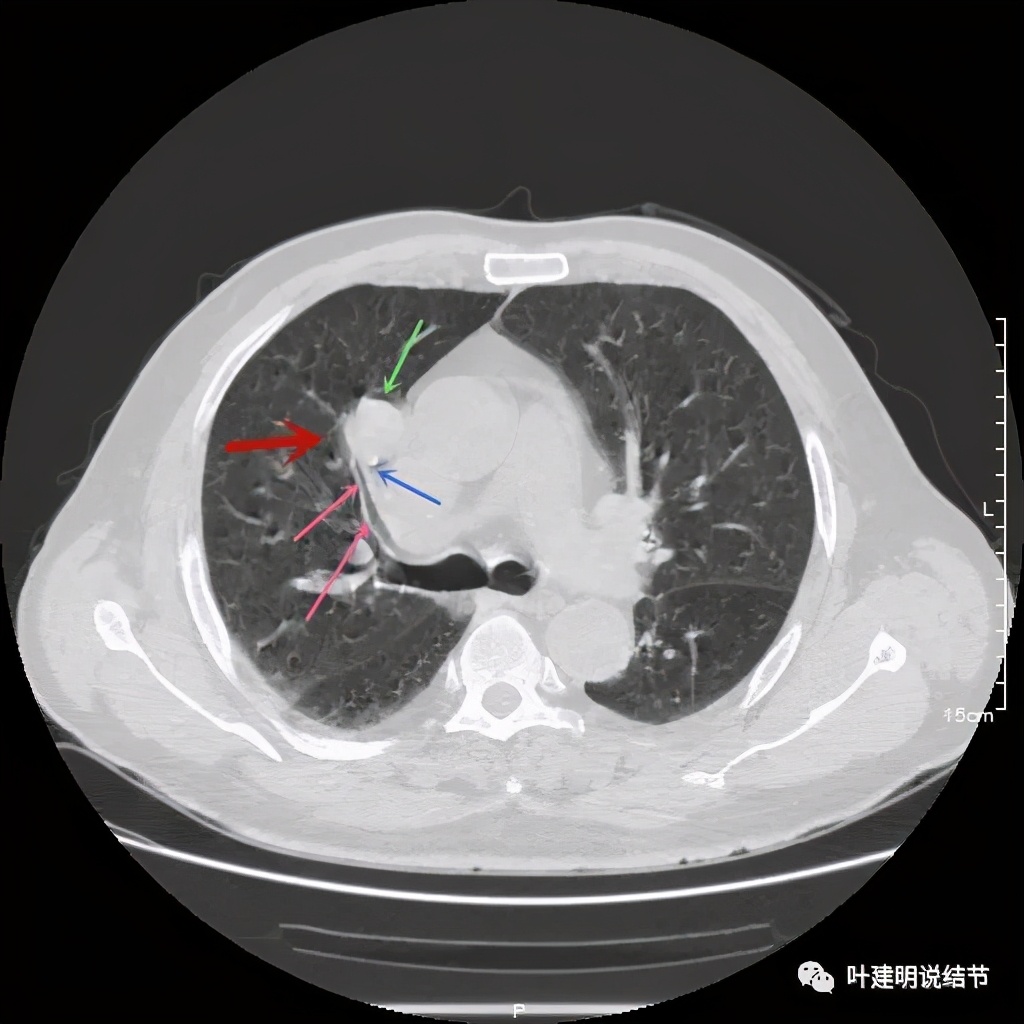

上图示病灶密度不均,但边缘过于光滑(绿色);支气管似有截断(粉色);局部有点状钙化(蓝色)

上图也示病灶密度不均,但边缘过于光滑(绿色);支气管似有截断(粉色);局部有点状钙化(蓝色)

病灶在上图层面似见支气管也是贴壁的。那么增强后又是如何呢?